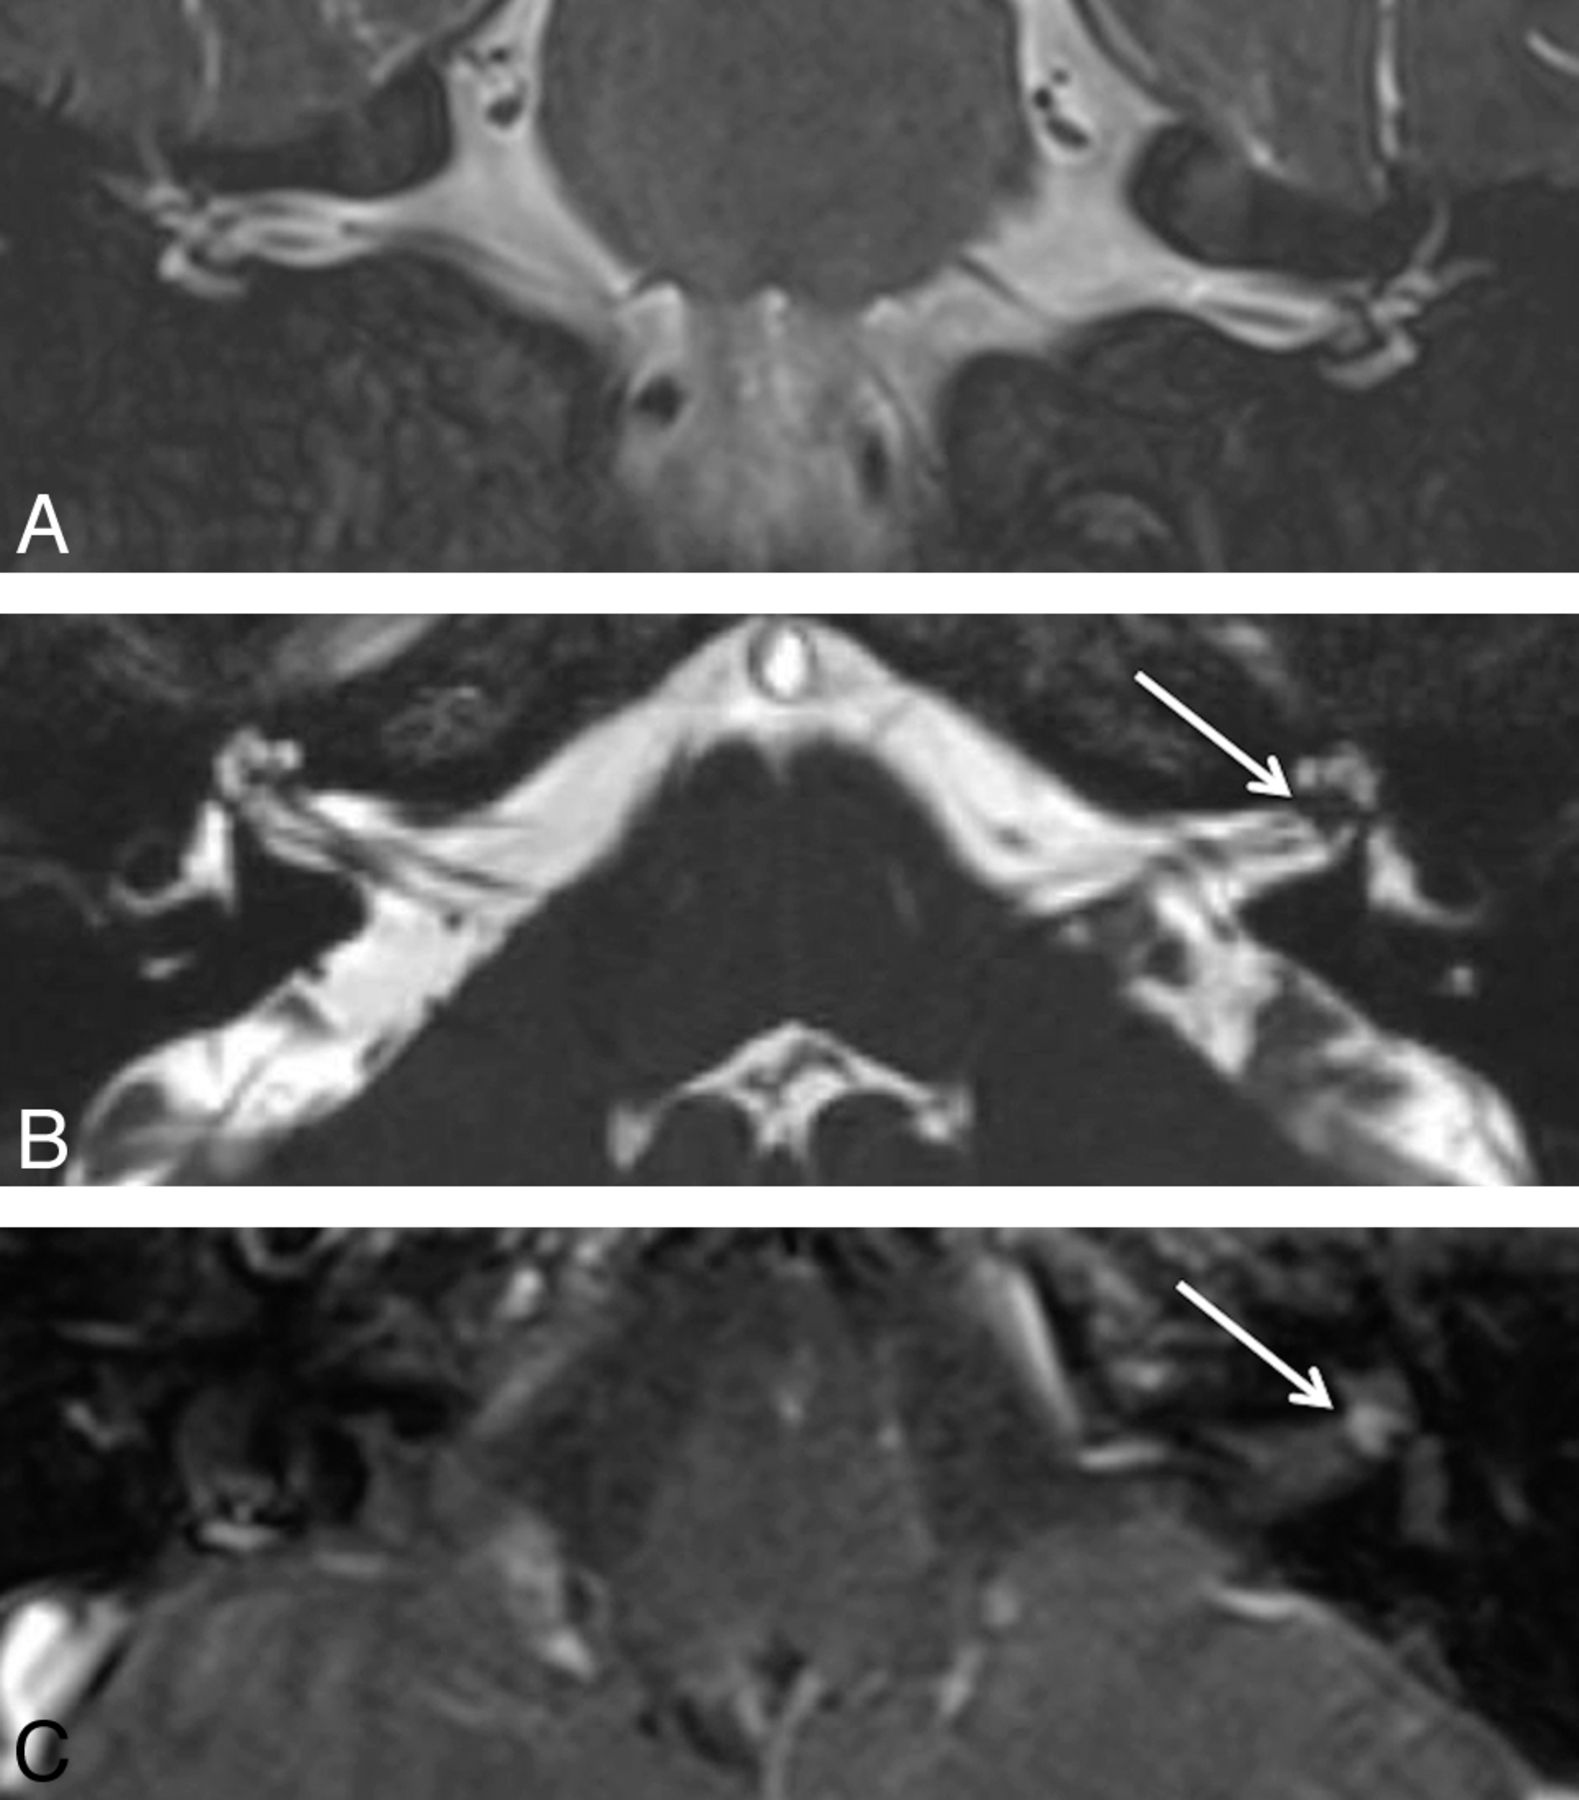

A 65-year-old woman who presented with left-sided hearing loss. A, Coronal T2WI shows the intracanalicular bilateral vestibulocochlear and facial nerves without associated lesion. B, Axial CISS image demonstrates a hypointense lesion (arrow) to better advantage located within the fundus of the left IAC. C, Postcontrast axial T1WI confirms the enhancing 2-mm lesion (arrow).

Observer 1 had 2 false-positives on the axial sequence and 2 false-positives on the coronal sequence, whereas observer 2 had 4 false-positives on the axial and 0 false-positives on the coronal sequence. Using both sequences, observer 1 had 2 false-positives and observer 2 had 1 false-positive, which was a different patient from observer 1. On retrospective review, the 3 false-positives generated on evaluation of both sequences were felt to be secondary to volume averaging from the adjacent wall of the IAC, banding artifact on the axial CISS that was not resolved on the coronal T2WI, and volume averaging from the anterior inferior cerebellar artery within the IAC (Fig 3).